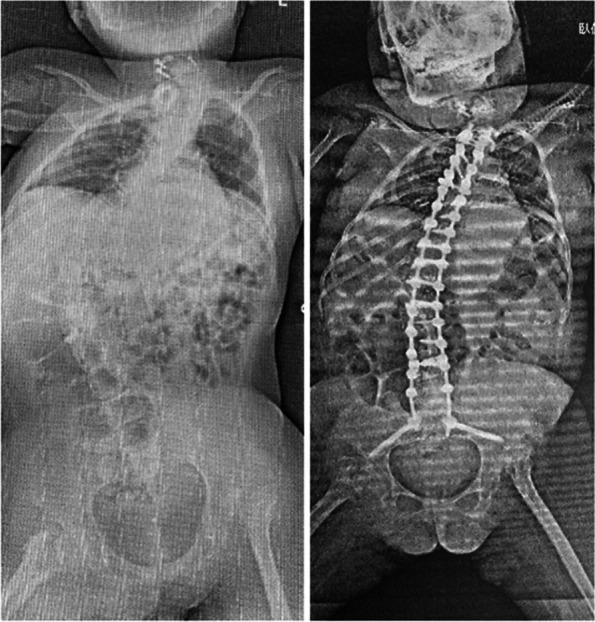

A 2 years and 6 months old girl, who was injured in a traffic accident, was diagnosed with C3 CSCI, resulting in complete quadriplegia and respiratory paralysis below C3. Thus, she was managed with a ventilator. Rehabilitation for quadriplegia, respiratory dysfunction, and autonomic neuropathy was started on the fifth day after the injury while she was in the intensive care unit. Six months after the injury, the patient was transferred to a hospital. Thereafter, she was discharged with nursing and care guidance provided to her family and environmental changes at home. Afterwards, she continued to acquire skills through writing training using a mouse stick, computer operation training, and electric wheelchair operation training, which enabled her to improve her ADL despite her severe disability. In terms of education, she was able to go through a regular elementary school, a regular junior high school, and then to a senior high school of a support school.

一名 2 岁零 6 个月大的女孩在交通事故中受伤,被诊断为 C3 CSCI,导致 C3 以下完全四肢瘫痪和呼吸瘫痪。因此,她使用呼吸机进行管理。在损伤后第 5 天,她在重症监护病房开始接受四肢瘫痪、呼吸功能障碍和自主神经病的康复治疗。受伤后 6 个月,患者被转至医院。此后,她在家庭护理和环境改变的指导下出院。之后,她通过使用鼠标棒进行书写训练、计算机操作训练和电动轮椅操作训练继续获得技能,尽管她残疾严重,但仍能提高 ADL。在教育方面,她能够顺利完成普通小学、普通初中,然后进入支持学校的高中。